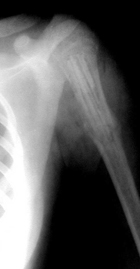

| Рисунок 2. Больная К. 15 лет. Аневризмальная киста левой бедренной кости. Пластика дефекта губчатыми аллоимплантатами: | ||

| а) рентгенологическая картина состояния до операции; | б) состояние после операции; | в) через 3 месяца после операции; |